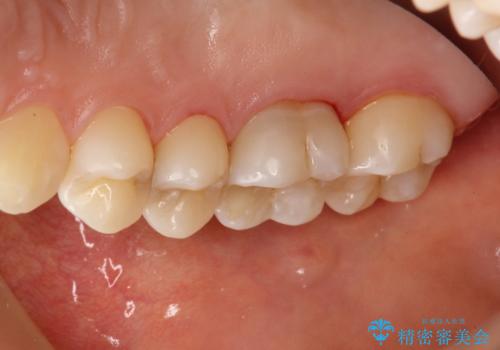

- 約3か月ごとにPMTCを行っている方です。定期的にメンテナンスしているためPMTC30分コースで全体のクリーニングが可能でした。

歯の表面は磨けていても、歯茎の境目や歯と歯の間の磨き残しはとても多いです。そのため、定期的にメンテナンスを行い、どこに磨き残しがあるか確認したり、歯磨きの仕方について指導を受けることが大切です。